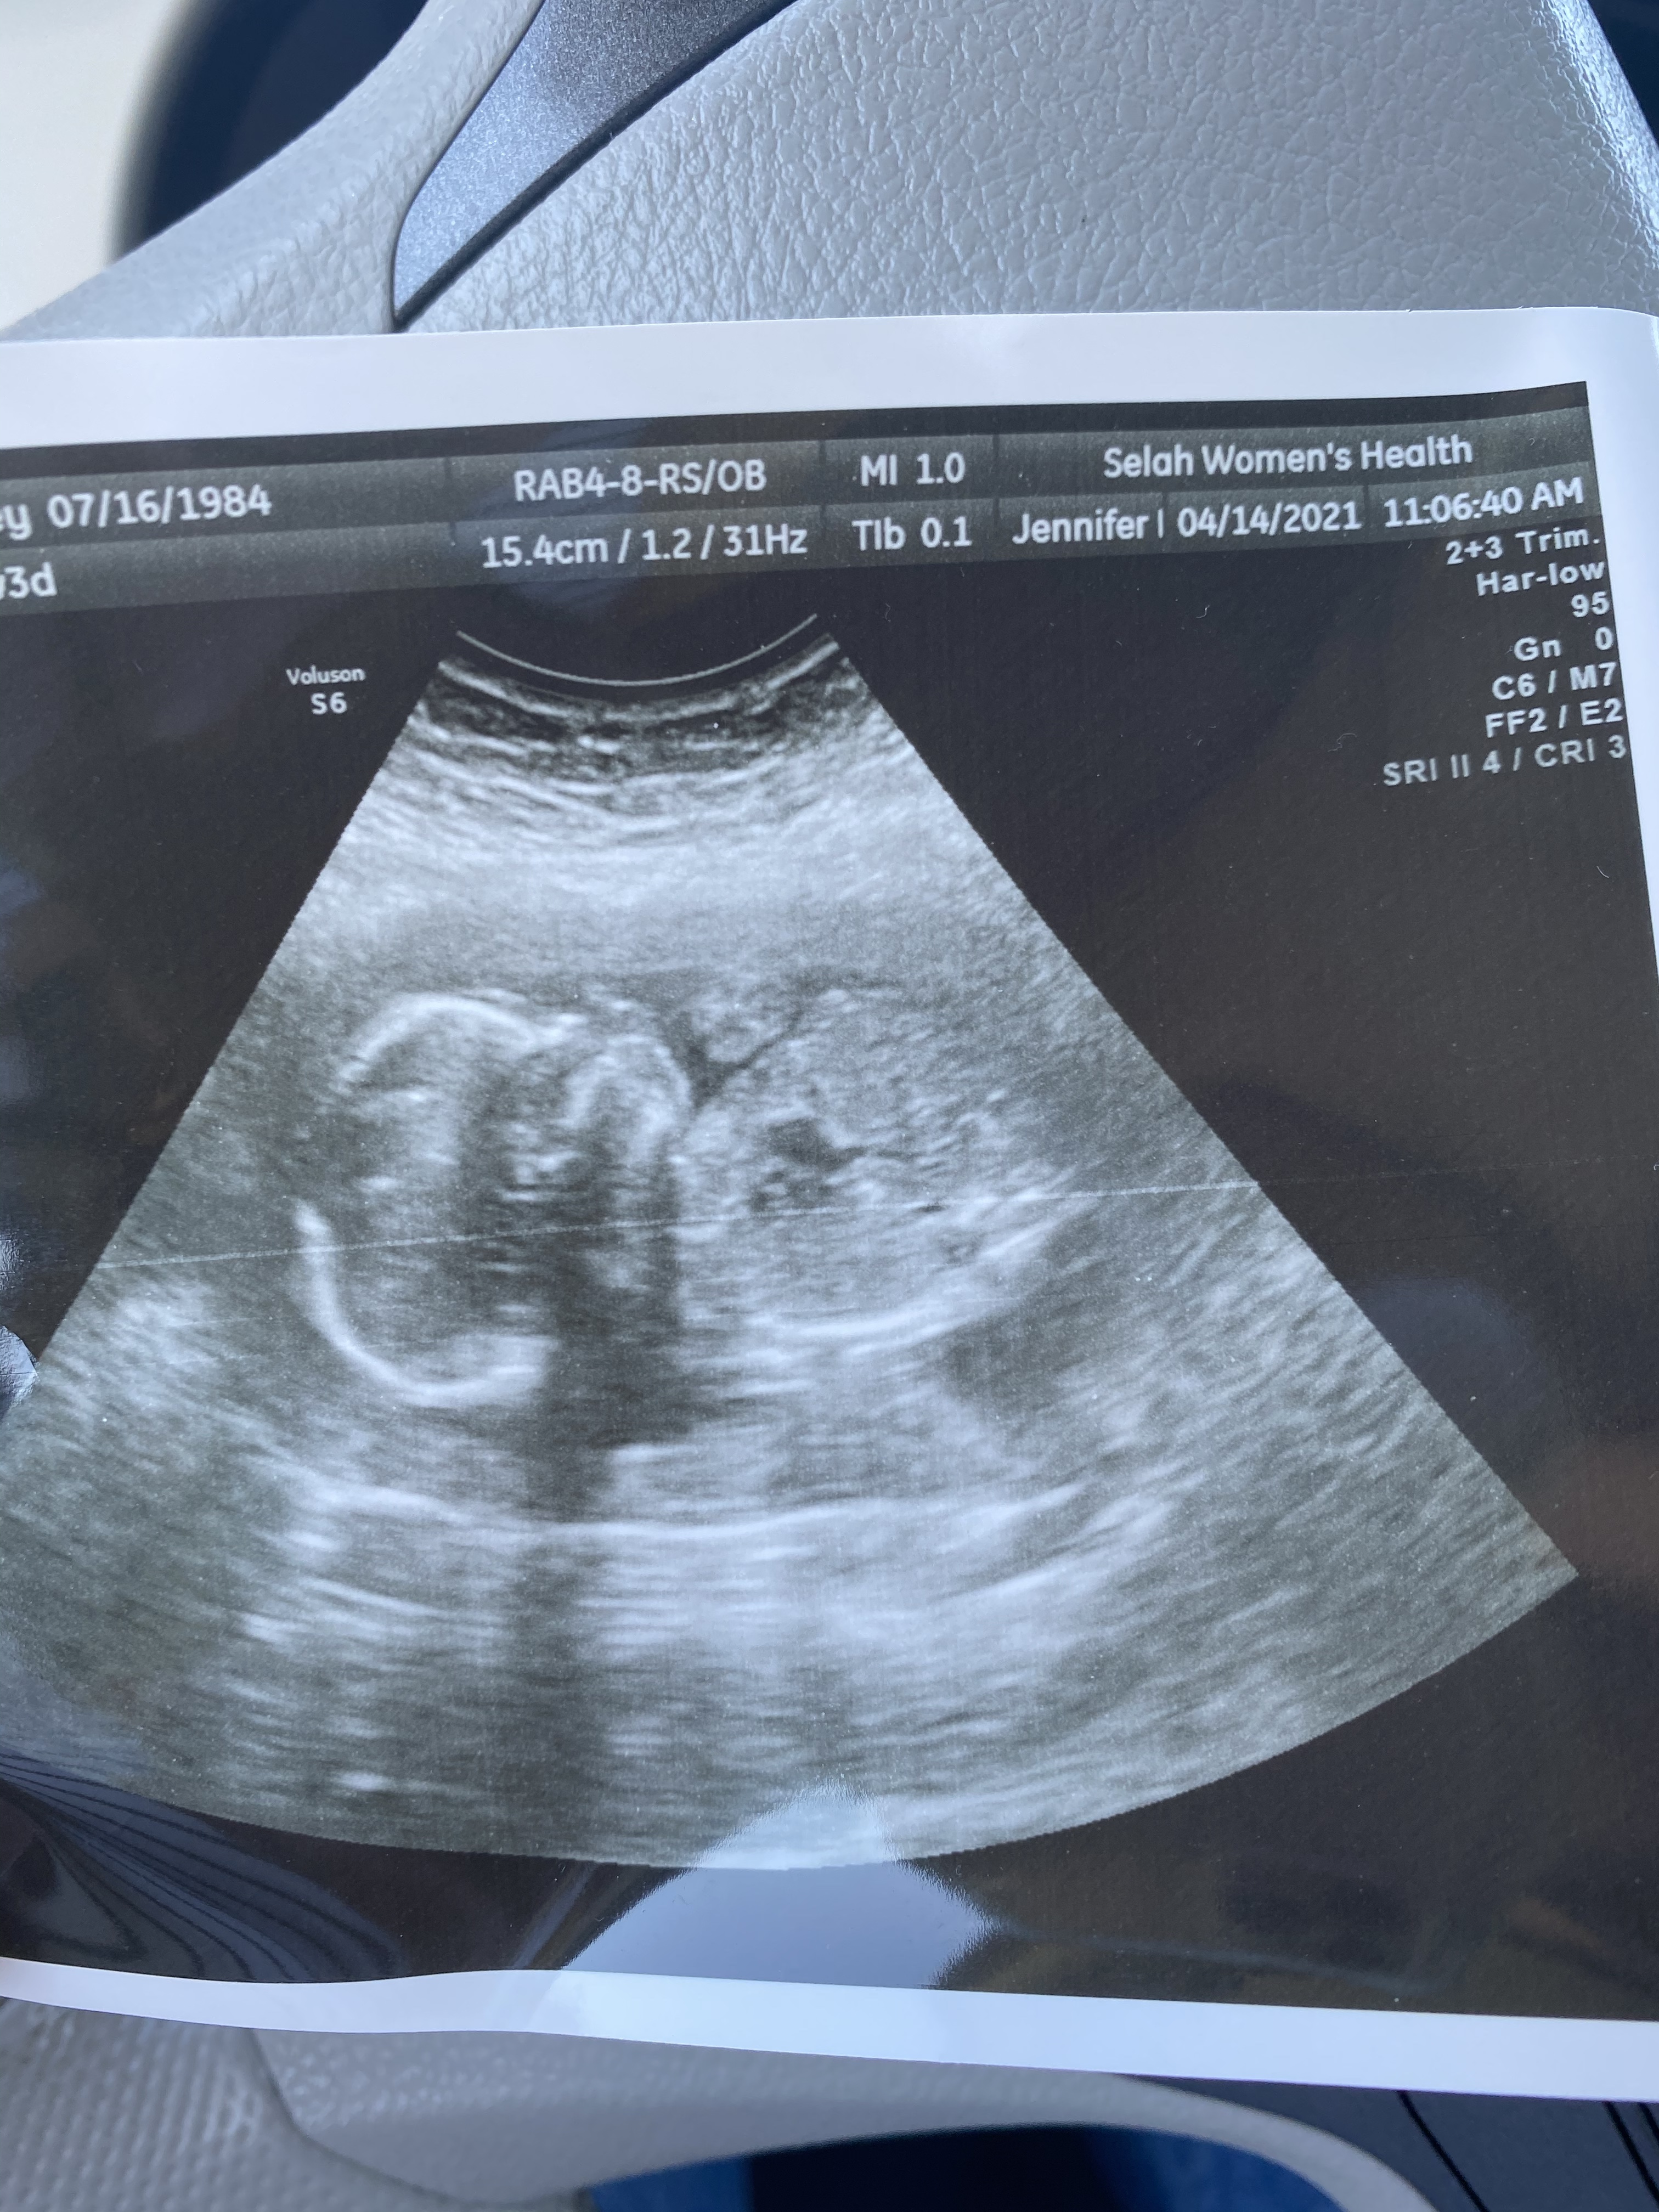

At 12 weeks we told the kids. I could hardly squeak the words out, I was just so excited especially for Isabelle. The kids couldn’t believe it. At 14 weeks we got our panorama results back- I met Jazz in the parking lot of the hospital and we clicked on the link together. Normal chromosomes, gender: female. Cue all the sobbing. Feels to good to be true.

Bless Dr. Kang. I’ll never be able to repay her for all the kindness and care she has given us over the years. She is not currently working OB patients, she has stepped back and doing all GNO services. But, she kept seeing me for months and months, at first it was to get to 12 weeks, then 16, then 20. Then to our fetal echo appointment down at Davis. Finally we transferred to Dr. Williams at about 28 weeks. I miss her, but she has so generously offered to be at the c-section as the second physician. I could just cry thinking about it- I know if she is there, we will be okay.

Anatomy scan and echo down at UC Davis went well- this sweet baby looks perfect in every way. At 28 weeks I tested positive for gestational diabetes (cmon now really.) and have spent the last two months monitoring everything I eat and testing my blood sugar four times a day. It has sucked. I mean, it is great in that I am eating healthy, not packing on extra weight, and keeping my numbers in check. But it has sucked as far as no birthday cake or bowls of cereal or comfort food. I’m sure I will be thankful in the long term but for now I just miss the freedom to eat like a pregnant lady.